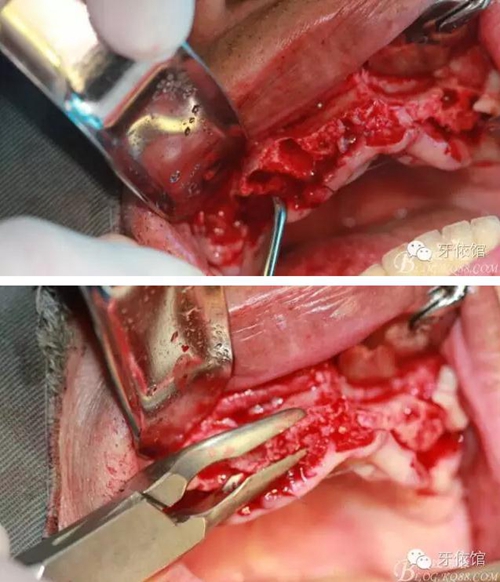

術(shù)中口內(nèi)照

降低骨高度,左右1,2骨寬度嚴(yán)重不足,決定將前牙2——2區(qū)間植體植在切牙孔內(nèi)

這個(gè)角度看1,2牙位骨寬度是不是很???僅2mm

用擴(kuò)孔鉆去除切牙孔內(nèi)神經(jīng)纖維和血管